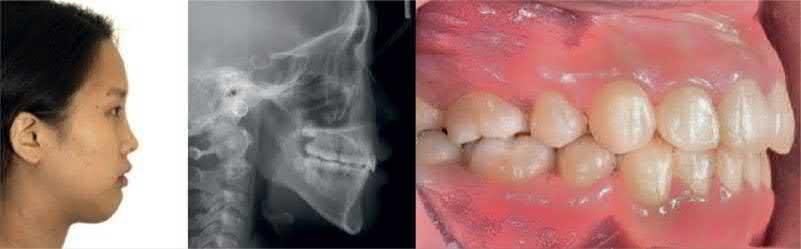

The introduction of TADs into orthodontics not only enables effective anchorage reinforcement with individual TADs, but also enhances the functionality of conventional orthodontic appliances when they are combined with TADs. For example, pendulum appliances anchored to the maxillary bone with TADs have achieved a similar amount of maxillary molar distalization to that of conventional pendulum appliances without TADs, providing significant premolar distalization in potentially less total treatment time and without the problem of anchorage loss [6]. For correction of Class III malocclusion with dental midline discrepancy, TADs can be used with sliding jigs (Figure 1.1) [7]. TAD‐supported Herbst appliances have significantly reduced unfavorable adverse treatment effects such as mandibular incisor proclination [8]. Placing a miniplate on the infrazygomatic buttress and linking it to the outer bow of a facemask has allowed protraction of the maxilla without any undesirable tooth movement that might cause unwanted arch length loss [9]. As an esthetic and simplified treatment option, a double J‐hook retractor and palatal TADs can be used to close extraction spaces by retracting the

maxillary anterior segment [10]. The use of a double J‐hook significantly reduced treatment time with the fixed appliances. Therefore, this might be a viable treatment option for patients who are reluctant to use conventional fixed appliances (Figure 1.2).

Figure 1.2  Class II correction with a double J retractor [10]. (a) Initial examination indicated a Class II Division 1 malocclusion with anterior crowding. (b) Schematic illustration shows a double J retractor and palatal TADs: palatal TADs (1, 2); anterior lever arm hooks (3); posterior lever arm hooks (4). (c) A double J retractor was connected to the TADs with elastomeric chains to achieve bodily translation. (d) Anterior tooth tipping can be controlled by adjusting the extension line of the force. (e) Maxillary anterior teeth were retracted and the extraction spaces were completely closed. (f) Maxillary anterior teeth were retracted and slightly tipped lingually. (g) Maxillary incisors were retracted after treatment. Source: Park et al. [10]. Reprinted with permission from Elsevier.